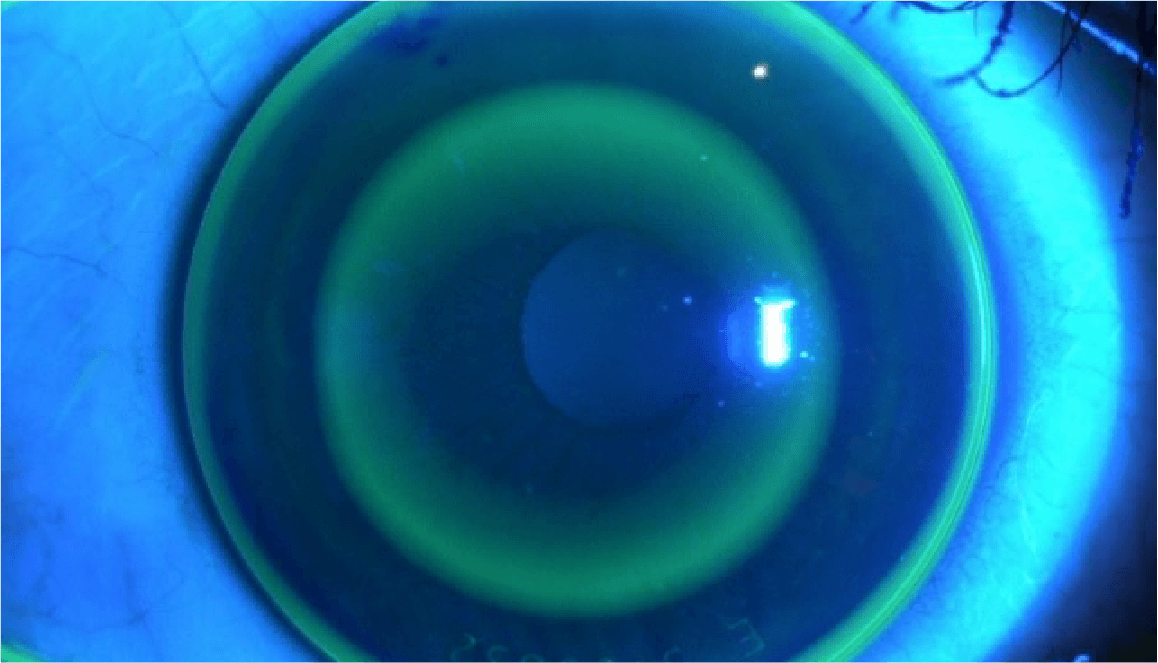

近視は幼児期、学童期、思春期を通し、主に眼の長さが伸びることで、焦点の合う距離が近くなり、焦点距離が近くなればなるほど遠くの像がぼやけてしまいますので、視力が低下します。

近視はなぜおこり、なぜ進行する?

近視にはもともと備わっているピント調節機能が関わっています。

眼は近くを見るときには調節力を使ってピントを合わせています。

目にする対象物が近い距離にあればあるほど、この調節力を強く使わなければなりません。

これが問題となり以下の機序が働き、近視は発症し、進行すると考えられています。

- 遠視性デフォーカスと調節ラグ

- 近くを見るときに発生しやすいピントの

合わせすぎのこと

- 軸外収差

- 目の中に入ってきた像を網膜が感じ取りますが、

網膜の中心から少し離れた場所におこるぼやけのこと